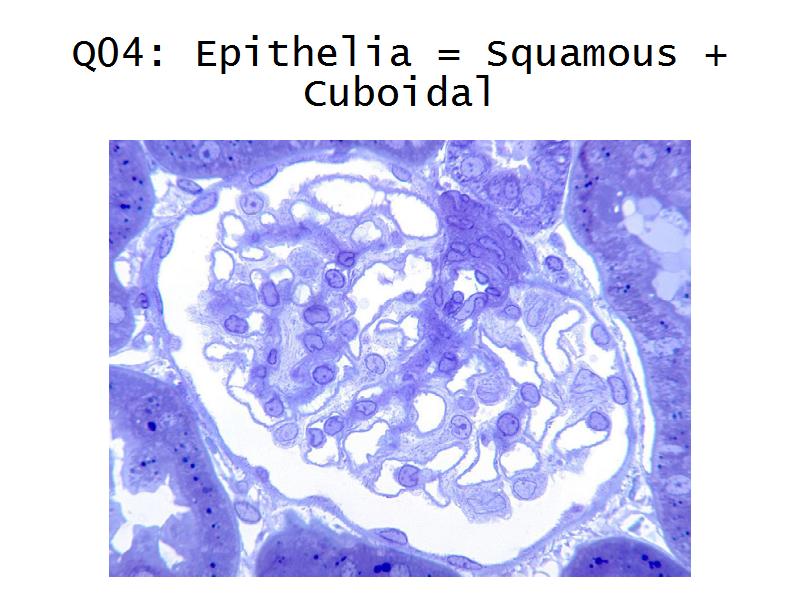

Q13: Name 1 epithelium for each.

- Kidney =

Q13: Name 1 epithelium for each.

- Kidney = cuboidal, squamous